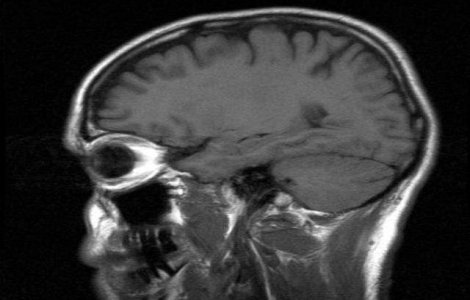

Echipa multidisciplinara care il evalueaza permanent pe Gabriel Cotabita a decis, marti, ca artistul sa faca un nou RMN cerebral, iar analiza a indicat zone cu leziuni grave, potrivit unor surse apropiate cantaretului.